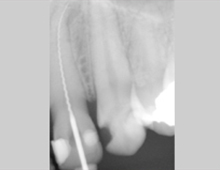

Bei der Wurzelbehandlung wird der Zahn unter örtlicher Behandlung aufgebohrt und der erkrankte oder abgestorbene Zahnnerv entfernt. Anschließend wird der Wurzelkanal gereinigt, desinfiziert und mit einer Wurzelfüllung versorgt. Das Pulpa-Füllmaterial zeichnet sich durch höchste Gewebefreundlichkeit und Volumenstabilität aus.

Eine Wurzelbehandlung erfordert höchstes zahnärztliches Können und Fingerspitzengefühl. So ist das Auffinden und Aufbereiten der teilweise sehr engen, gekrümmten Wurzelkanäle schwierig und erfordert einen längeren Behandlungsaufwand. Wir verwenden modernste und flexible Instrumente, sie sorgen für eine sichere und effiziente Wurzekanalaufbereitung.